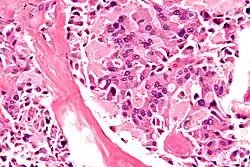

| Micrograph of medullary thyroid carcinoma, as may be seen in MEN 2b. H&E stain. | |